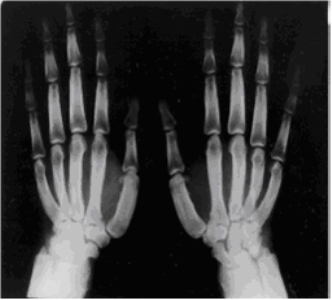

При этом патологическом состоянии наблюдается гипертрофия поверхностного костного слоя – надкостницы, которая приобретает бугристый вид, по краям плоских костей образуются локальные утолщения – наросты, осуществляется рост костных образований по ширине, а на суставных сочленениях, в участках, где фиксируются сухожилия и связки, формируются шипы из костной ткани, так называемые остеофиты. Гипертрофированные ногтевые фаланги придают пальцам вид барабанных палочек, а ногтевая пластинка становится по форме часового стекла.

- Рентгенисследование (в т.ч. КТ), МРТ дают возможность вывить гипертрофию надкостницы и деформирование дистальных частей трубчатых костей, существование наростов из кости в местах фиксирования сухожильно-связочного аппарата, замещение костно-мозговых проходов губчатым веществом.